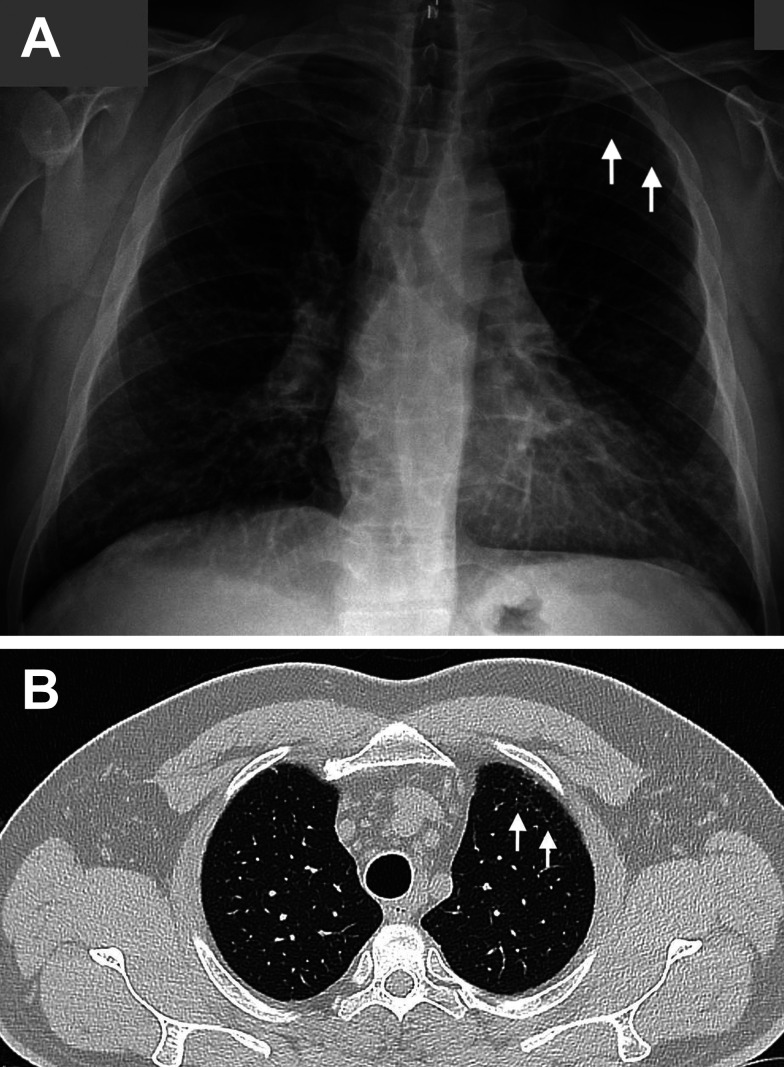

矽肺病是一种因吸入结晶化合物而引起的纤维化呼吸系统疾病。特别是在所有使用二氧化硅的行业中,如喷砂、石凳制造、陶瓷、珠宝和玻璃生产,都应该考虑到这一点。Sjögren综合征(SS)是一种缓慢进展的全身性自身免疫性疾病,其特征是慢性淋巴细胞侵袭外分泌腺和腺外组织,并伴有一系列全身性症状。职业二氧化硅暴露已知与自身免疫性疾病有关,如系统性硬化症和系统性红斑狼疮。本文介绍了一个陶瓷工人Sjögren综合征的病例。

Silicosis is a fibrotic respiratory disease caused by inhalation of crystalline compounds. In particular, it should be taken into account in all professions where silica is used, such as sandblasting, stone bench manufacturing, ceramics, jewelry and glass production Sjögren's syndrome (SS) is a slowly progressive systemic autoimmune disease characterized by chronic lymphocytic invasion of exocrine glands and extraglandular tissues, accompanied by a series of systemic symptoms. Occupational silica exposure is known to be associated with autoimmune diseases such as systemic sclerosis and systemic lupus erythematosus This manuscript presents a case of Sjögren's syndrome in a ceramic worker.